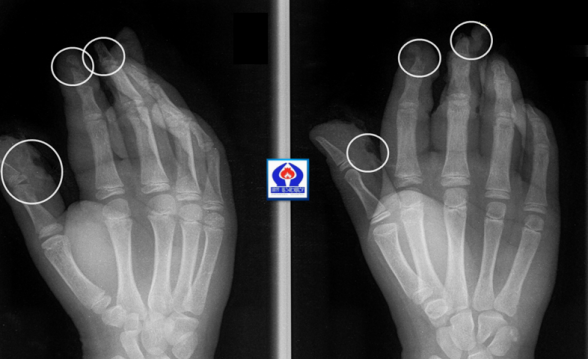

Ամանորի գիշերը «Սուրբ Աստվածամայր» ԲԿ են ընդունվելհրավառության տարբեր տեսակներից տուժած չորս երեխաներ, տարբեր աստիճանի վնասվածքներով:

Երեխաներից երկուսի մոտ եղել են անդամահատված մատներ, ճայթուկը պայթել է հենց ձեռքերի մեջ, մյուս երկուսի մոտ համեմատաբար թեթև վնասվածքներ են եղել:

«Սուրբ Աստվածամայր» ԲԿ-ի պլաստիկ վիրաբույժների կողմից երեխաները վիրահատվել են և դուրս գրվել հիվանդանոցից: